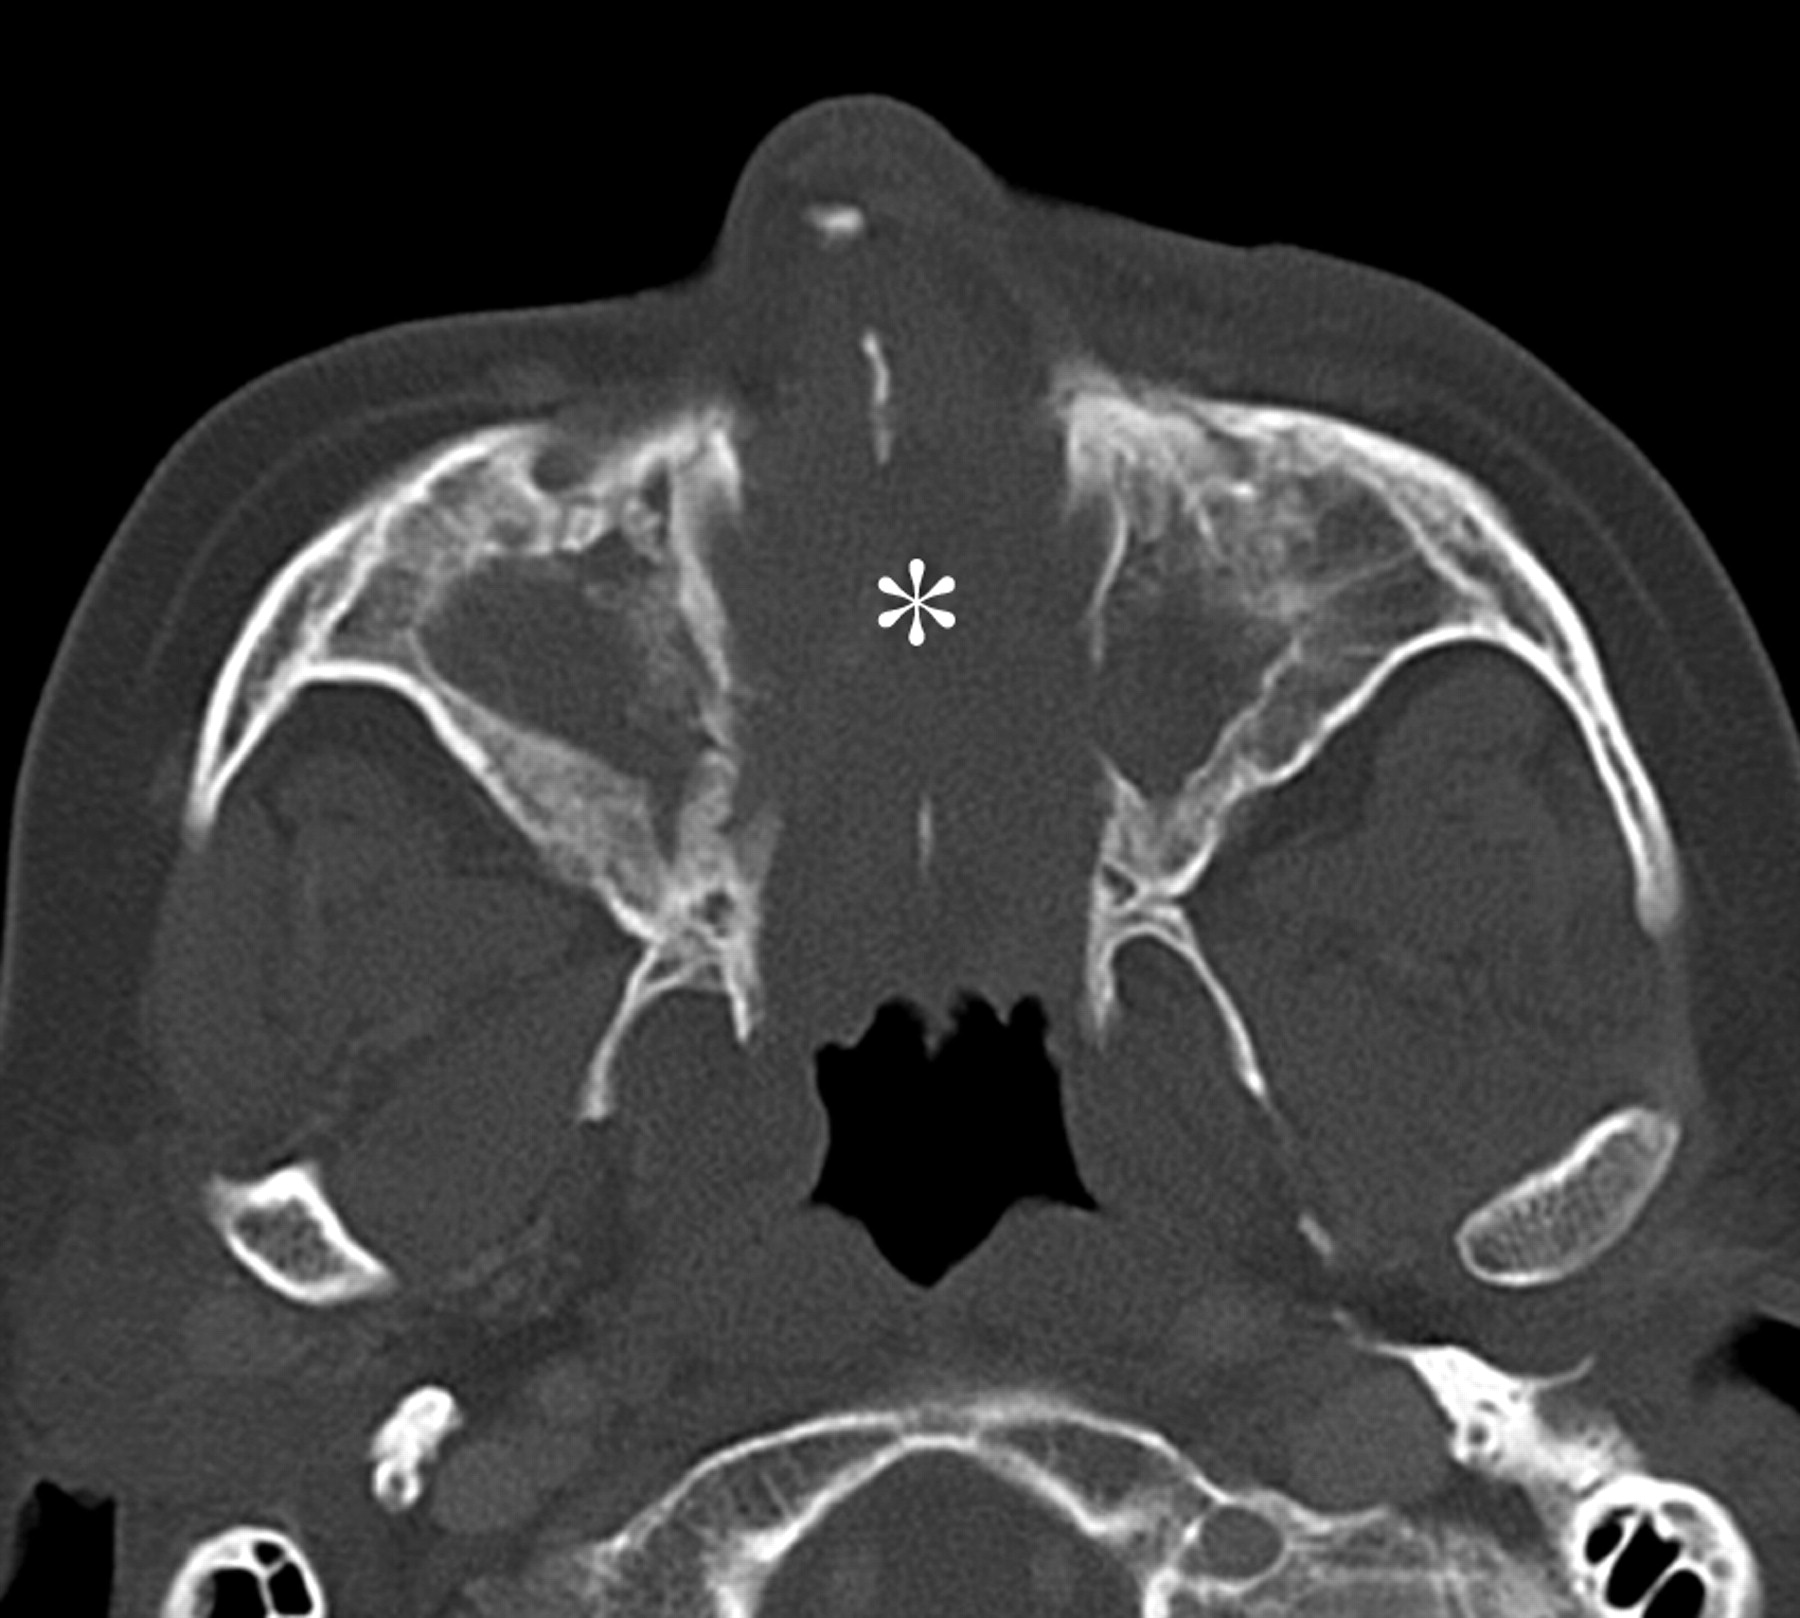

Гранулематоз Вегенера

Ринолит.